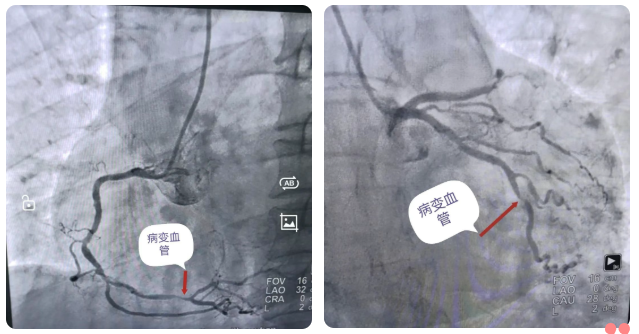

什么是冠状动脉造影

冠状动脉造影是一种用于直接观察心脏供血血管(冠状动脉)的微创检查。通过心导管经皮穿刺入腕部的桡动脉或腹股沟处的股动脉血管,沿主动脉逆行至升主动脉根部,然后探寻左或右冠状动脉开口,注入造影剂,同时用X光机拍摄动态影像,从而清晰显示冠状动脉有无狭窄、堵塞及其位置和程度,是诊断冠心病的金标准。

冠状动脉造影是诊断冠心病的“金标准”,其主要意义在于直接观察冠状动脉的形态、狭窄位置和严重程度。它通过向冠脉注入造影剂,利用X线成像清晰显示血管阻塞情况,不仅能确诊冠心病,还能精准评估病变范围与性质,为后续治疗方案(如药物、支架植入或搭桥手术)提供关键依据,是指导有效治疗的核心检查手段。

心血管造影+支架植入术齐发力

冠脉造影术通过手腕或者大腿仅2毫米的微创穿刺,导入导管直至心脏冠状动脉。高清数字减影血管造影(DSA)设备实时生产血管三维影像,精准定位狭窄部位、程度与范围,为治疗提供“导航级”依据。而冠脉支架植入术是对确诊的严重狭窄(狭窄程度≥70%)或急性心梗患者,植入合金网状支架,撑开堵塞血管,恢复血流,治疗“立竿见影”。手术全程局部麻醉、患者清醒,耗时短,恢复快。万医心内科已全面开展心血管造影+支架植入术,双管齐下,解决您的“心”困扰。